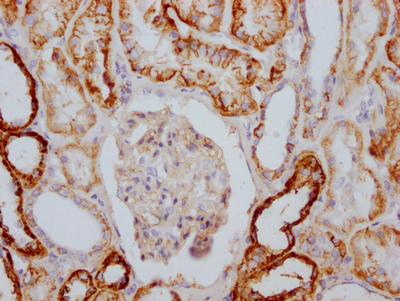

BackgroundThis is the catalytic component of the active enzyme, which catalyzes the hydrolysis of ATP coupled with the exchange of sodium and potassium ions across the plasma membrane. This action creates the electrochemical gradient of sodium and potassium ions, providing the energy for active transport of various nutrients.

DescriptionATP1A1 Recombinant Monoclonal Antibody [4C3]. Unconjugated. Raised in: HEK293F Cell.

ImmunogenA synthesized peptide derived from human Sodium Potassium ATPase

ApplicationELISA, IHC; Recommended dilution: IHC:1:50-1:200